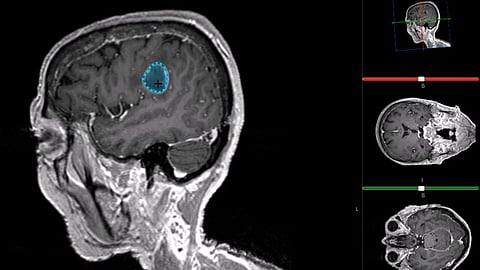

Gliomas are the most common primary brain tumours and originate from the glial cells of the brain. They are a heterogenous spectrum, from slow-growing to highly-aggressive infiltrating tumours.

Nearly half of all Glioma’s are classed as high-grade gliomas (HGG) and, due to their highly aggressive nature, have a dismal prognosis with an average survival of only 4.6 months without treatment and approximately 14 months with today’s optimal multimodal treatments.